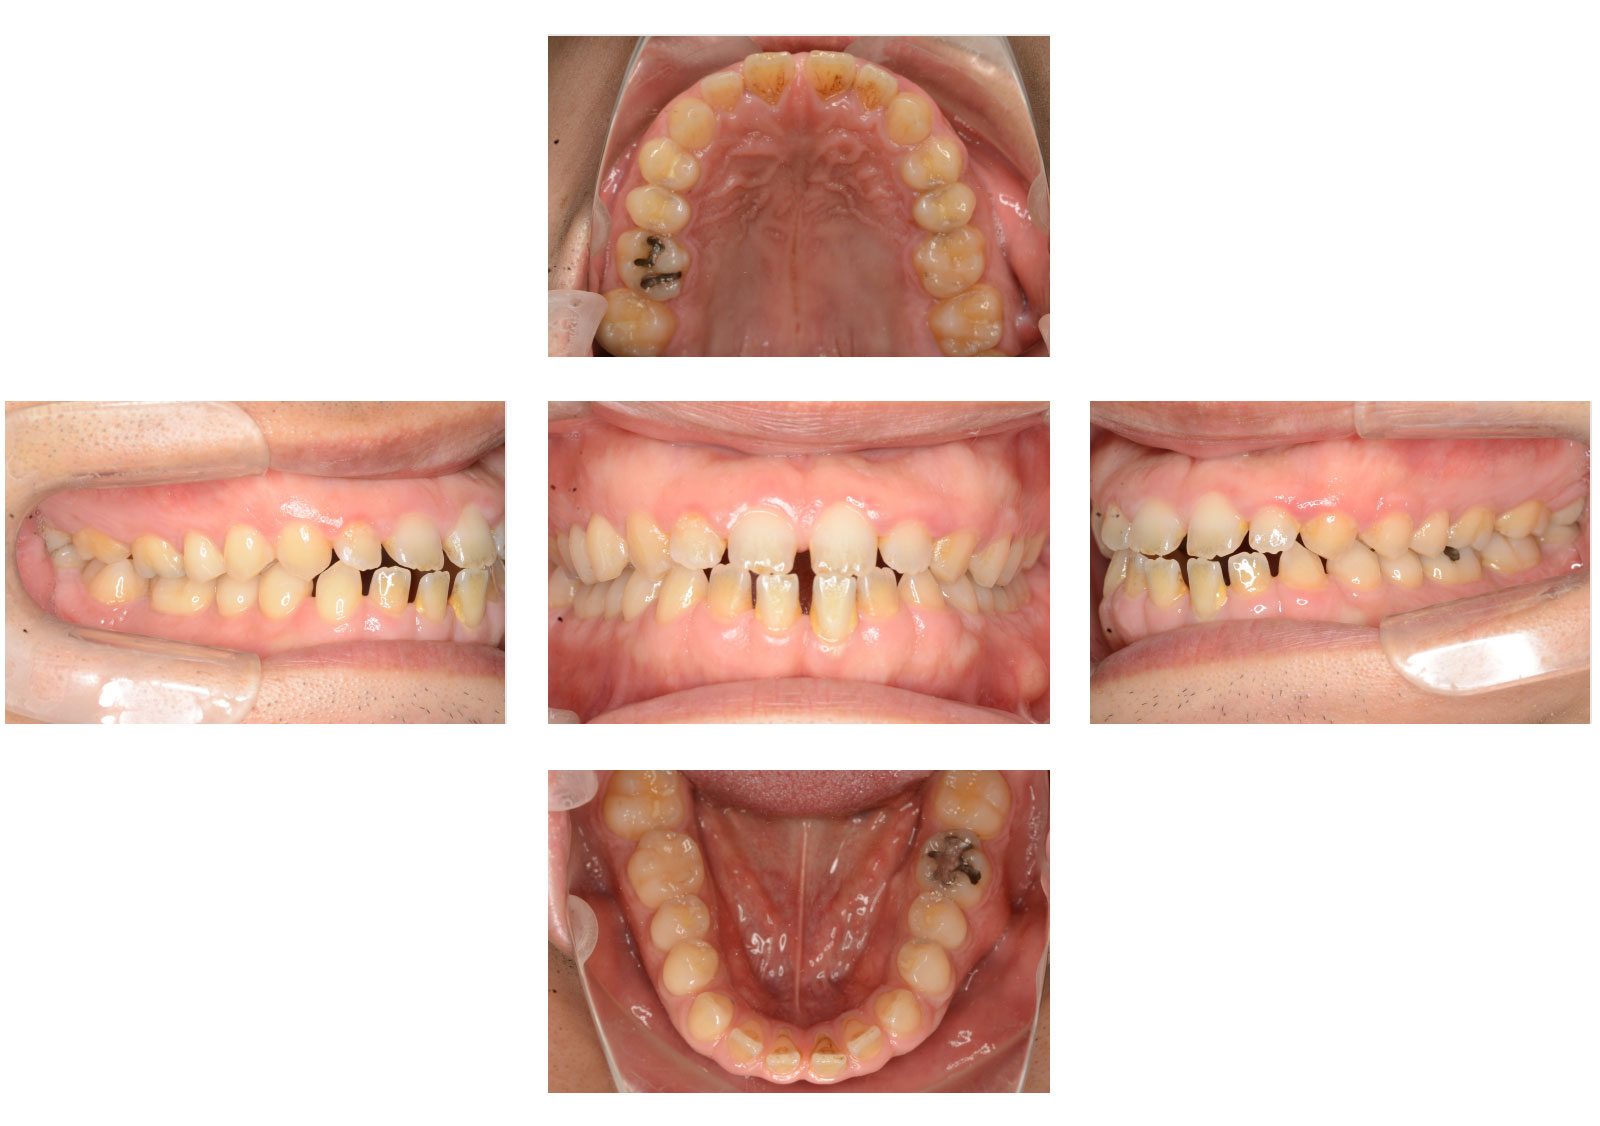

空隙歯列(くうげきしれつ)は、歯と歯の間にすき間が生じて、歯の裏側にある舌が見えたり、歯と歯の間が黒く見えたりする不正咬合です。一般的に「すきっ歯」とも呼ばれます。下顎前突(受け口)など、他の不正咬合と同時に起こることもあります。

症例画像